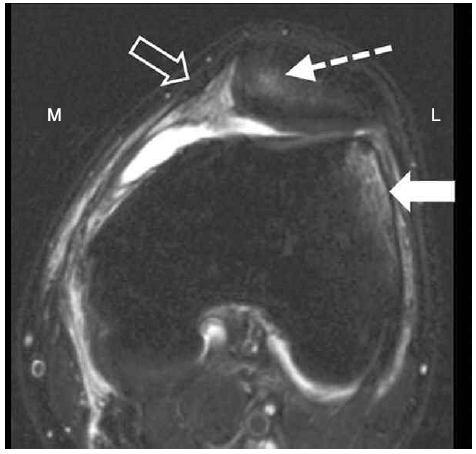

△ 그림 46-10. 일과성 외측 슬개골 탈구 (Transient lateral patellar dislocation)

슬개골을 지나는 축면 지방 포화 T2 강조영상은 외측 대퇴과의 후외측 방면(굵은 화살표)과 내측 슬개골 후관절(점선 화살표)에서의 상호 골타박상(높은 신호)을 보여준다. 내측 지대(빈 화살표)는 주위 부종으로 두꺼워져 있고, 부분 파열을 나타낸다. M = 내측, L = 외측